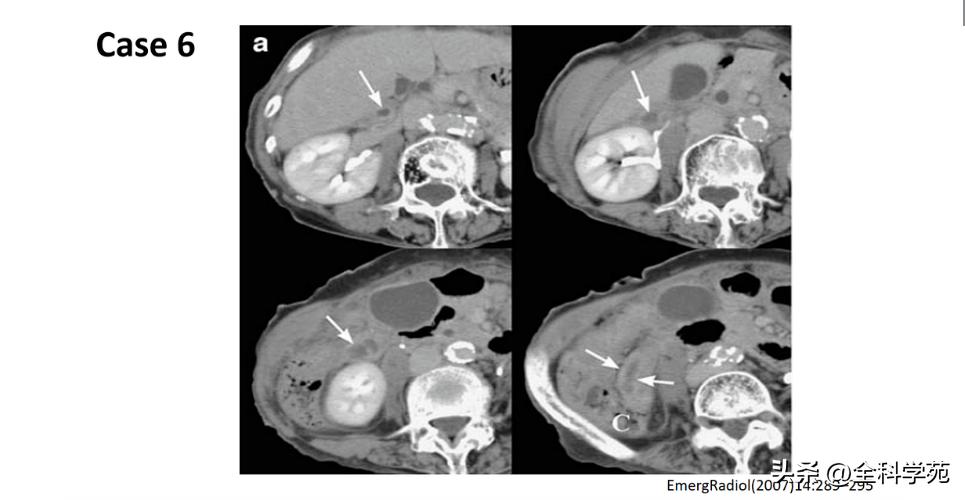

◆ 穿孔 (Perforation)

◆ 局部低强化是穿孔征象

◆ 蜂窝织炎和脓肿 (Phlegmon and abscess

◆ 门静脉炎 (Pylephlebitis)